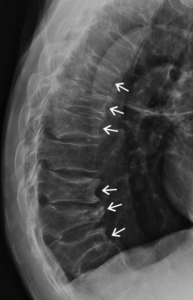

In Case 20 of the 2017.2 KFP you visit Betty, an 80 year old who presents with acute upper back pain that happened while gardening. She has a history of late menarche and early menopause, had 3 years of HRT before ceasing. Spinal Xray was performed.

What are the abnormalities present in this Xray? (list 5)

- Kyphosis

- Wedge compression fractures

- Vertebral body osteophytes

- Degenerative changes of the intervertebral disc spaces

- Endplate sclerosis

- Thoracic vertebral crush fractures secondary to osteoporosis

This case focused on an older female patient presenting with acute onset of upper-back pain. Candidates were required to interpret the lateral spinal X-ray that was provided and identify the diagnosis of osteoporosis and provide appropriate initial investigations. These elements of the case were covered well by the majority of candidates; however, the final question requested non-pharmacological strategies to assist in ongoing management. This was not answered as well, with candidates providing either pharmacological advice or nonspecific advice, such as the commencement of vitamin D supplementation.